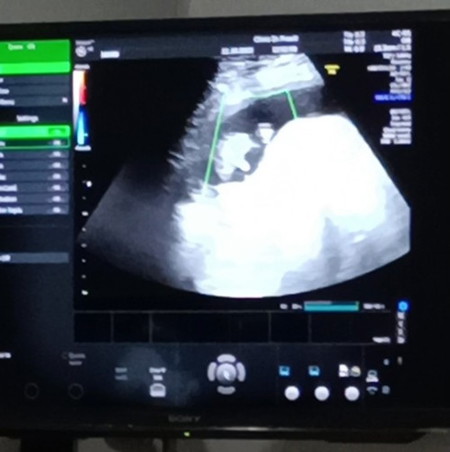

ตอนนี้น้องได้16 week แล้ว หมอบอกเราได้ผช. แม่ๆบ้านไหน รูปอัลตร้าซาวด์คล้ายเราบ้างคะ น้องเป็นผช. จริงๆใช่ไม๊😊😊

ของเรา ผช.ชัดเจนเลยค่ะ จู๋ชัดมากค่ะ (ฝั่งซ้าย) ฝั่งขวาคือหน้าน้องค่ะ